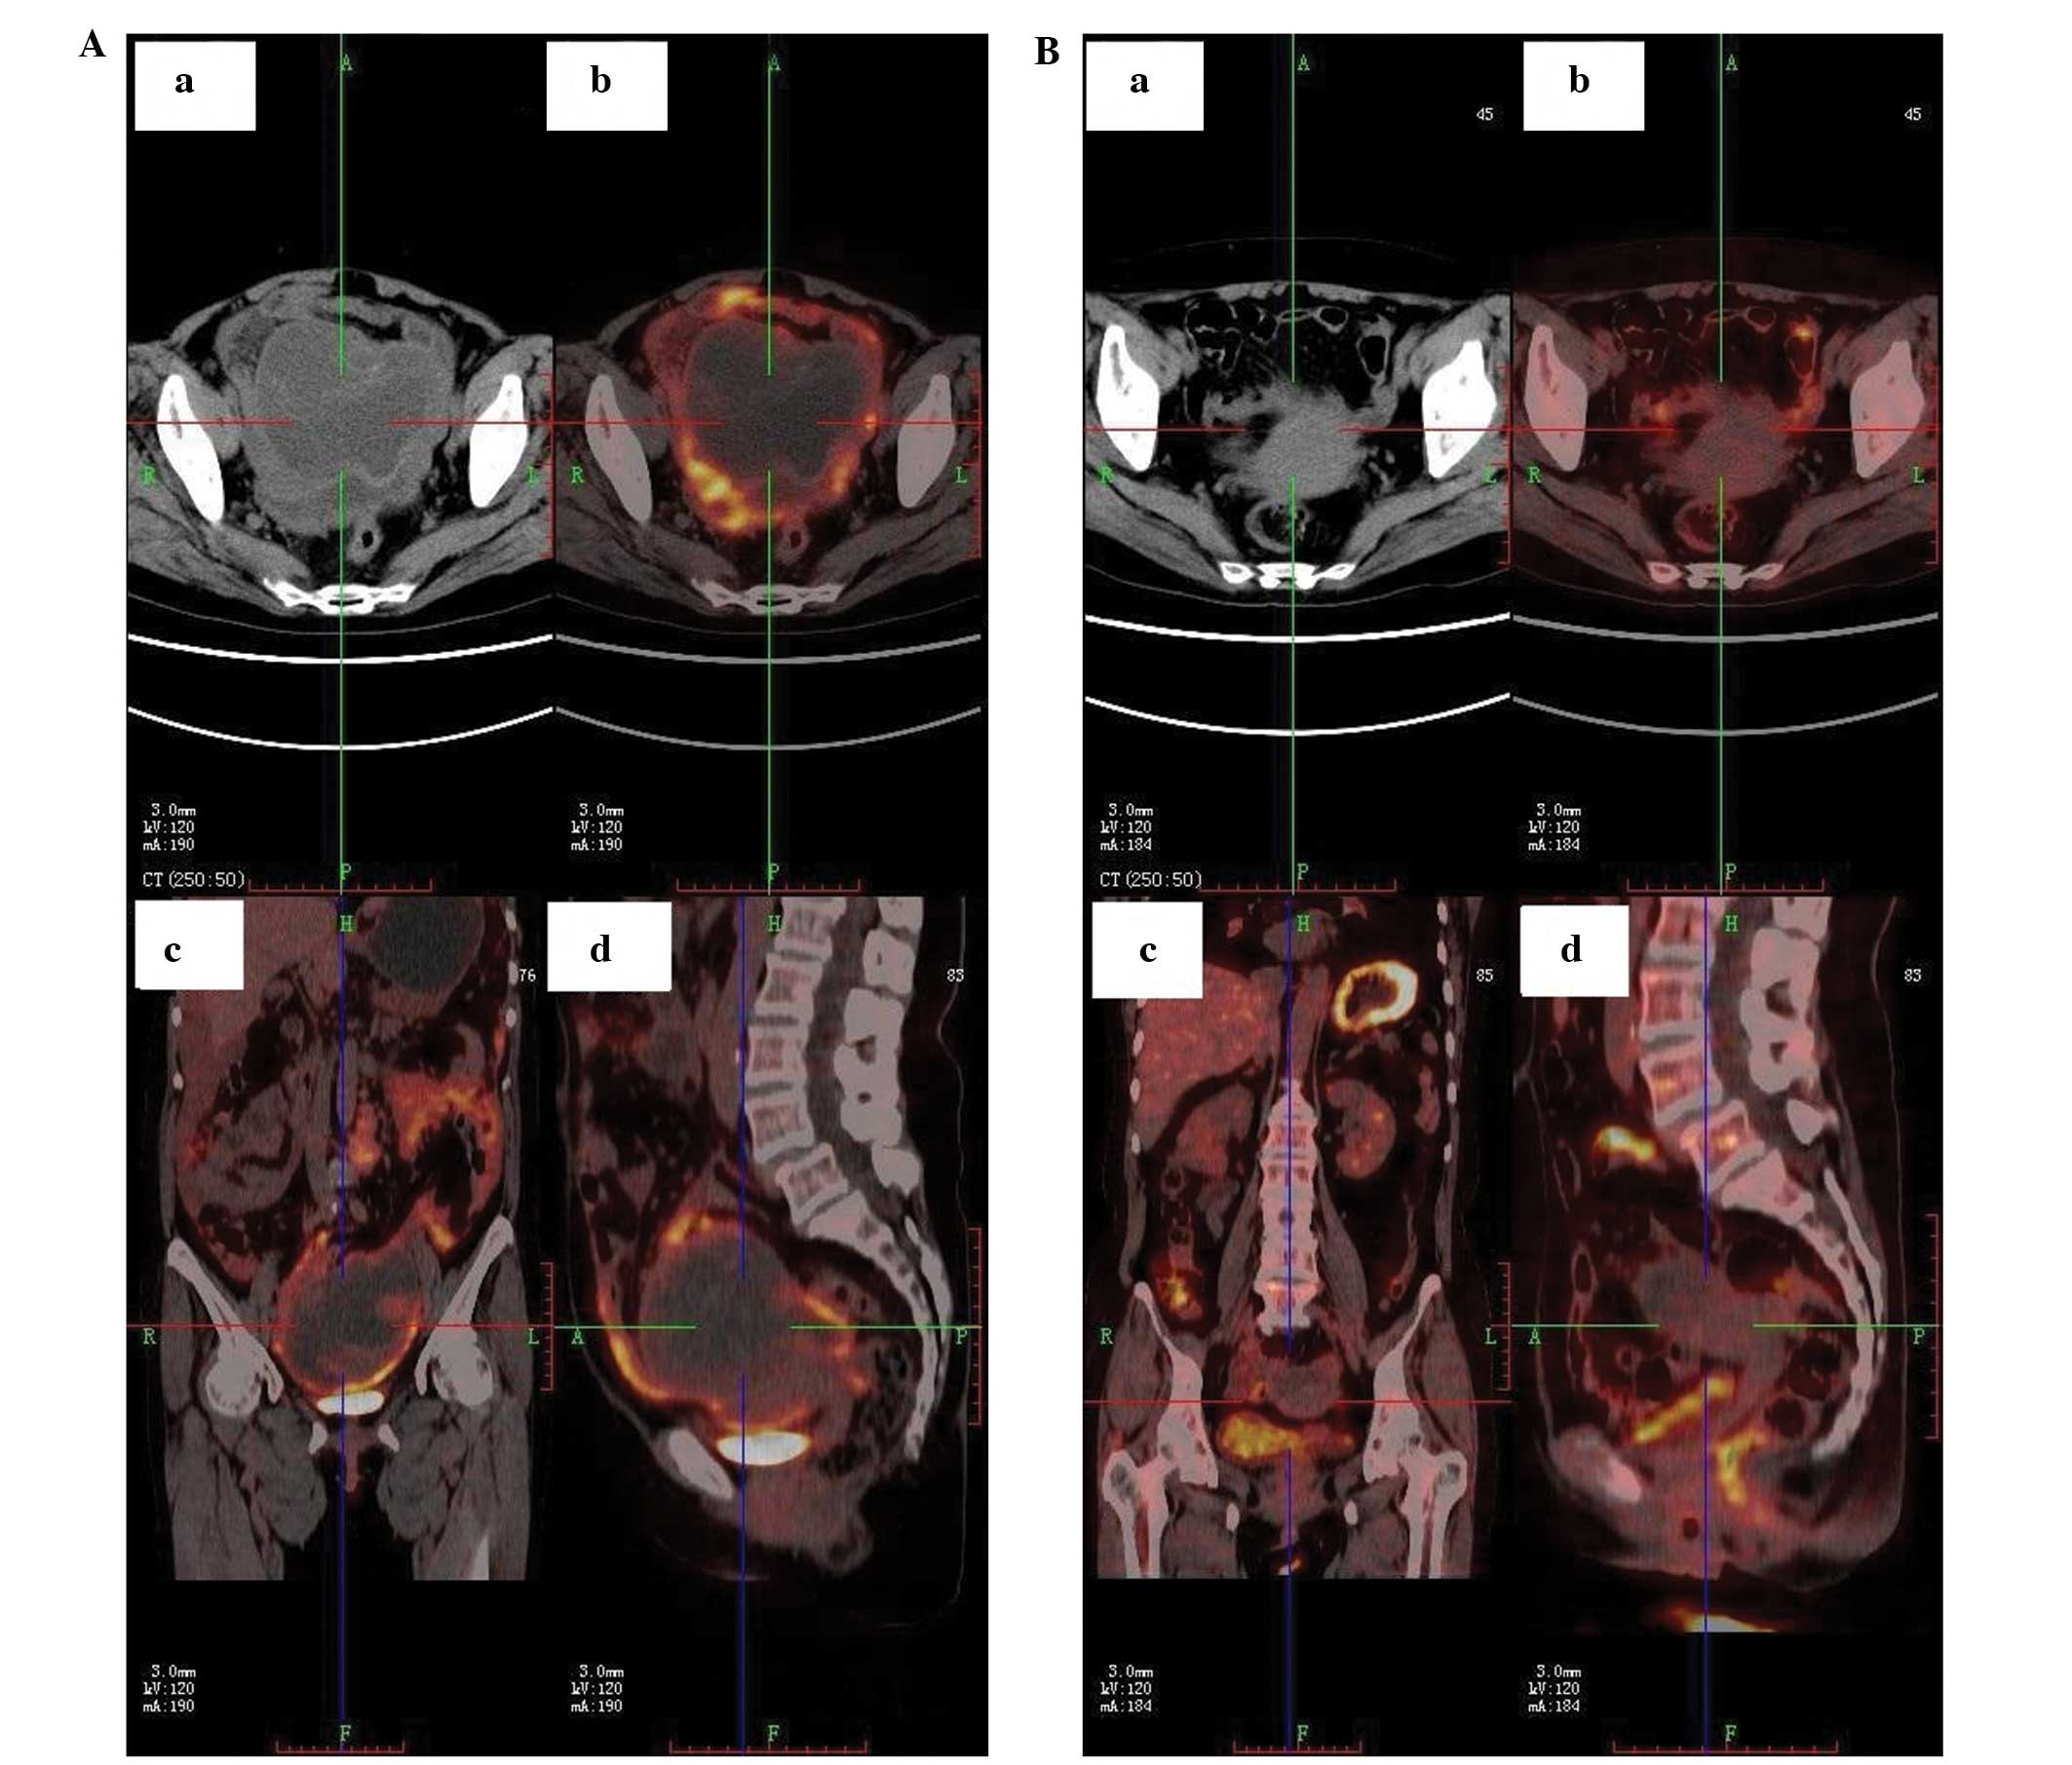

CASE REPORT Open Access Neoadjuvant radiotherapy of primary irresectable unicentric Castleman’s disease: a case report and review of the literature ... View Full Source